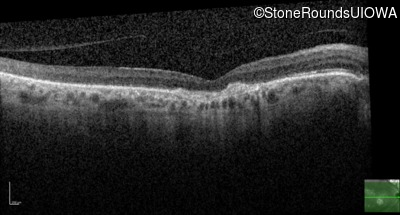

Optical Coherence Tomography - Right - 20/80

Exemplar / OCT Stack

OCT Stack